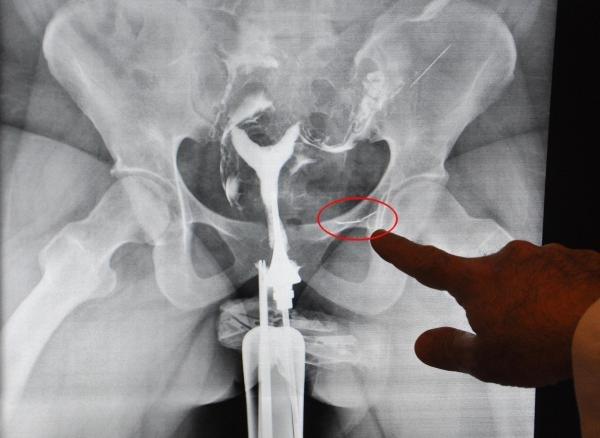

Başhekim olan Kadın Hastalıkları ve Doğum Uzmanı Opr. Dr. Rıdvan Erdemir ile görüşen S.Ş.'nin, çekilen röntgen filminde, rahim kanallarının tıkalı olduğu tespit edildi. Ayrıca filmde, mesane bölgesinde yabancı cisim görüldü.

Ameliyata alınan S.Ş.'nin çocuk sahibi olabilmesi için tedavisi yapılırken, mesane torbası dışına yapışmış görülen yabancı cismin de dikiş iğnesi olduğu belirlendi. Dikiş iğnesi, ameliyatla çıkarıldı.

Operasyon hakkında bilgi veren Opr. Dr. Rıdvan Erdemir ise, "Hastamız geldiğinde bize iğneden bahsetmedi. Çocuk tedavisi için çektiğimiz filmde, orada olmaması gereken yabancı bir cisim gördük. Ameliyatta çıkardığımızda cismin dikiş iğnesi olduğunu görünce şaşırdık. 16 yıl bu iğneyle yaşamış. İğne mideden bağırsaklara geçmiş, bağırsakları deldikten sonra mesane torbasının dışına yapışmış ve yağ bağlamış. İğne adeta karın boşluğunda dolaşmış. Önemli olan hayati organlara zarar vermemesi." diye konuştu.